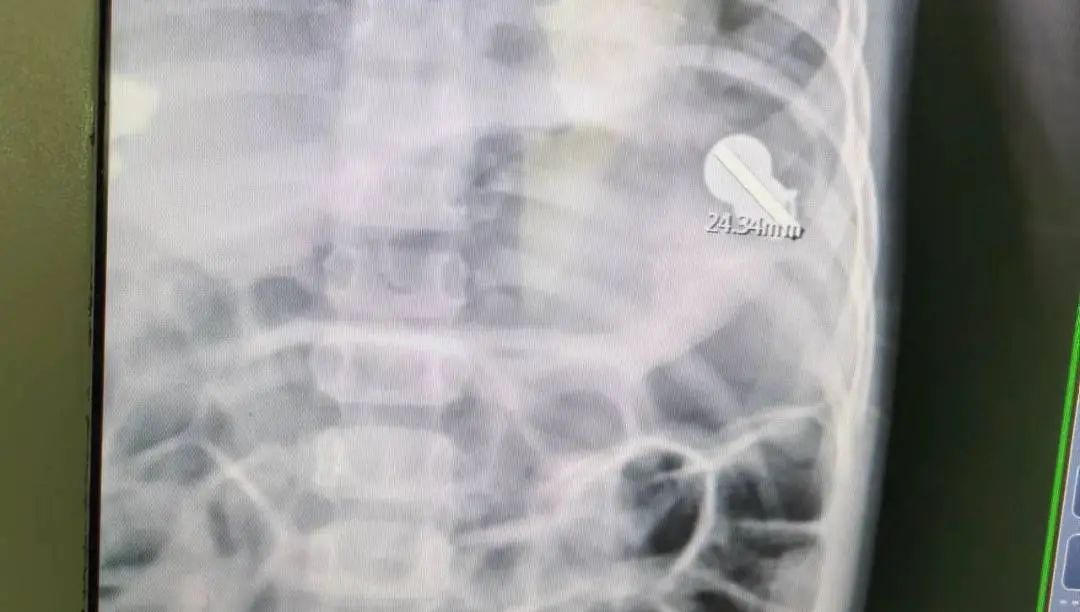

接诊的张医生询问情况后,安排了 X 光检查。检查结果颇为震撼:好家伙!胃里惊现 『订书针』

这枚订书针卡在幽门处,已经形成了两处 溃疡!小李挠了挠头,不好意思地说:「我一个没注意,喝中药的时候把订书针给吞了下去。」话不多说,赶紧安排无痛胃镜取出! 来一个胃镜检查。下取出异物「大赏」